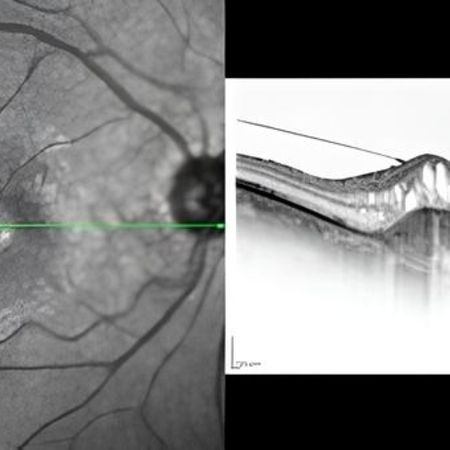

Optische Kohärenztomographie (OCT)

• Die tomographische Untersuchung, kurz OCT (Optische Kohärenztomographie) erstellt Querschnittsbilder der Netzhaut, des Sehnervs und der Hornhaut und ist eine wichtige Zusatzuntersuchung neben dem Spaltlampenmikroskop.

• Die Untersuchung ist nicht invasiv, ungefährlich, berührungslos und schmerzfrei.

• Mein Gerät nutzt die weltweit modernste Technologie und ermöglicht genaueste Diagnose über Erkrankungen der oben genannten Organe. Insbesondere für die Erkennung und Kontrolle der häufigen AMD (Altersabhängige Makula Degeneration), der Diabetischen Netzhauterkrankung und des Glaukoms (Grüner Star) ist die Optische Kohärenztomographie (OCT) von unschätzbarem Wert.

• Die OCT gehört heute zur Standarduntersuchung vieler Augenerkrankungen, die dann innerhalb kürzester Zeit diagnostiziert und dokumentiert werden können.